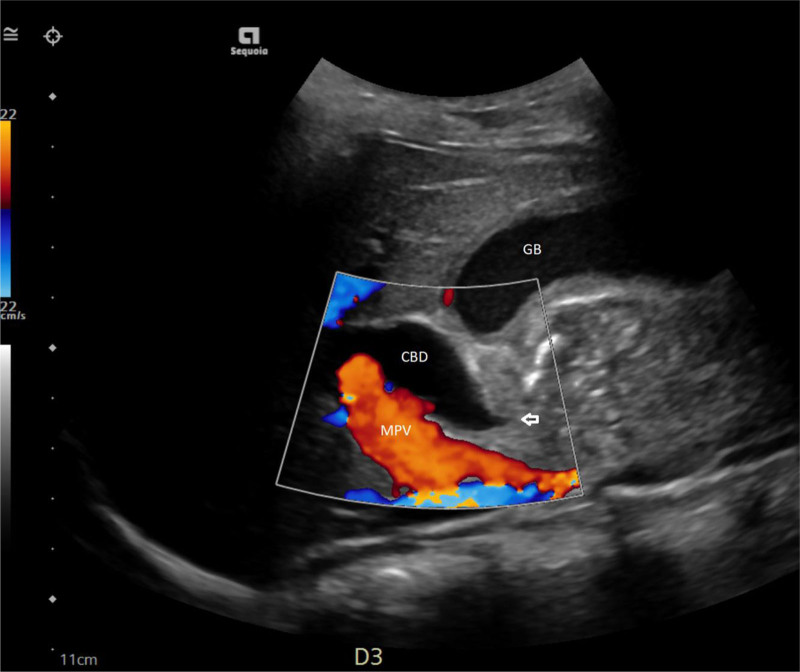

儿童幽门螺杆菌感染只占疾病的一小部分,而在发达国家,这一比例正在下降。典型的表现在文献中有很好的描述。我们报告了一位15岁的男性,他表现为黄疸、贫血、尿色深和腹痛,并被发现有幽门螺旋杆菌感染引起的十二指肠溃疡继发梗阻性黄疸。梗阻性黄疸是很少报道的十二指肠溃疡并发症,特别是在儿童。本报告回顾幽门螺杆菌感染,概述消化性溃疡疾病的并发症,并说明梗阻性黄疸作为儿童十二指肠溃疡的罕见表现。

Pediatric Helicobacter pylori infection represents a small proportion of disease that is otherwise decreasing in the developed world. Typical presentations have been well-described in the literature. We report a 15-year-old male who presented with jaundice, anemia, dark urine, and poorly characterized abdominal pain and was found to have obstructive jaundice secondary to a duodenal ulcer resulting from H. pylori infection. Obstructive jaundice is a seldom reported complication of duodenal ulcer, particularly in children. This report reviews H. pylori infection, outlines complications of peptic ulcer disease, and illustrates the rarity of obstructive jaundice as a presenting sign of duodenal ulcer in children.